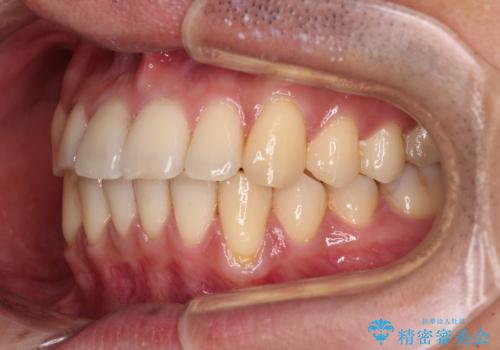

ワイヤー装置での上下前歯の部分矯正

- 上下前歯のデコボコを気にして来院された患者様です。

口元の突出感や奥歯の咬み合わせに問題がなかったため、インビザラインの廉価版パッケージを用いるか上下ワイヤー装置での部分矯正を提案しました。

部分矯正は咬み合わせが不安定になったり、スペースができてしまったりと、適用となる患者様は極めて限られますが、こちらの方はスムーズに治療を終えることができました。